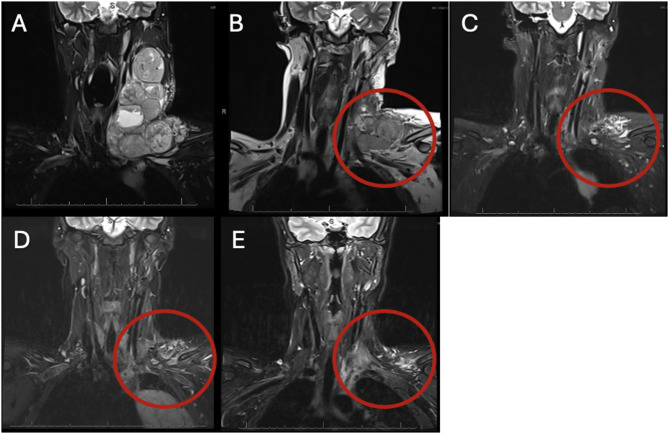

我们报告了一例起源于头部和颈部的广泛而庞大的儿童转移性黑色素瘤,该病例对抗程序性细胞死亡(PD-1)抑制和巩固的个性化超分割立体定向适应性放疗(PULSAR)联合治疗有明显反应。手术切除颈部后,患者最初接受抗pd -1和抗细胞毒性t淋巴细胞相关蛋白4 (CTLA-4)双检查点阻断免疫治疗,但很快疾病进展。他被转移到一种不同的抗pd -1免疫疗法,与酪氨酸激酶抑制剂联合使用PULSAR巩固局部治疗。这种联合治疗在纵隔的另一个部位进一步疾病进展之前达到了肿瘤缓解和无进展状态一年。由于其他方面疾病控制良好,继续进行单药抗pd -1免疫治疗,并对进展部位给予补救性PULSAR,再次导致肿瘤反应和6个月的无进展状态。在联合治疗后,没有较大部位的大体病变出现局部进展。本病例提示,PULSAR联合抗pd -1免疫治疗对小儿复发或难治性转移性黑色素瘤是有效的。临床试验号:不适用。

We present a case of extensive and bulky pediatric metastatic melanoma originating in the head and neck which markedly responded to combination therapy with anti-programmed cell death (PD-1) inhibition and consolidative personalized ultra-fractionated stereotactic adaptive radiotherapy (PULSAR). After surgical debulking with neck dissection, the patient was initially treated with anti-PD-1 and anti-cytotoxic T-lymphocyte associated protein 4 (CTLA-4) dual checkpoint blockade immunotherapy, but quickly had disease progression. He was transitioned to a different anti-PD-1 immunotherapy in combination with tyrosine kinase inhibitors in conjunction with consolidative local therapy using PULSAR. This combination therapy achieved tumor response and progression-free status for one year before further disease progression at a separate site in the mediastinum. Due to otherwise good disease control, single agent anti-PD-1 immunotherapy was continued and salvage PULSAR was administered to the progressive site, again resulting in tumor response and progression-free status for 6 months. None of the bulkier sites of gross disease had local progression after combination therapy. This case suggests that the synergistic effect of PULSAR and anti-PD-1 immunotherapy is efficacious for relapsed or refractory metastatic melanoma in pediatric patients. Clinical trial number: not applicable.